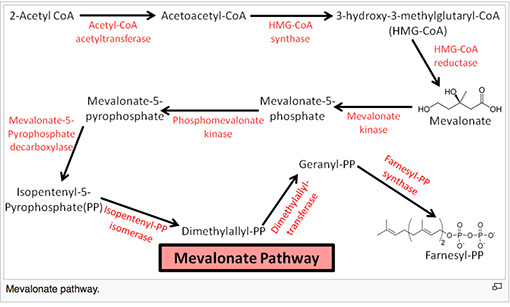

AR, inborn error of cholesterol synth, mutation in enzyme 7-Dehydrocholesterol reductase (DCHR7) causing hypocholesterolemia; missense mutations account for 87.6 of SLOS cases

- simvastatin is an inhibitor of HMG-CoA reductase and has been known to treat SLOS

Farnesyl PP eventually converts to lanosterol

Degradation of hypoxia induced factor 1 α (HIF α)